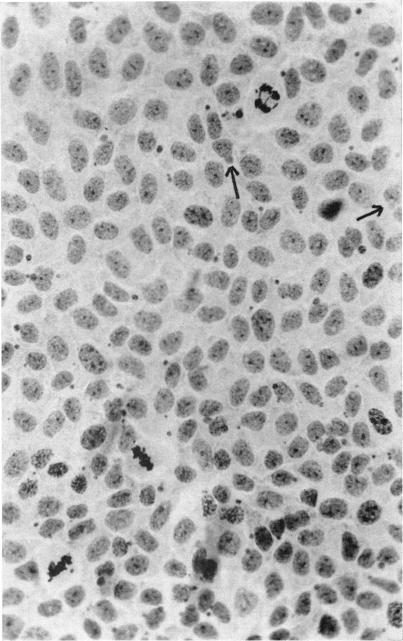

Changes in lens epithelium after x-ray or neutron irradiation (mouse and rabbit).

Trans Am Ophthalmol Soc. 1966;64:700-34.

Histologic studies of neutron- and x-irradiated mouse lenses.中子和X射线辐照小鼠晶状体的组织学研究。

Radiat Res. 1960 Nov;13:737-50.